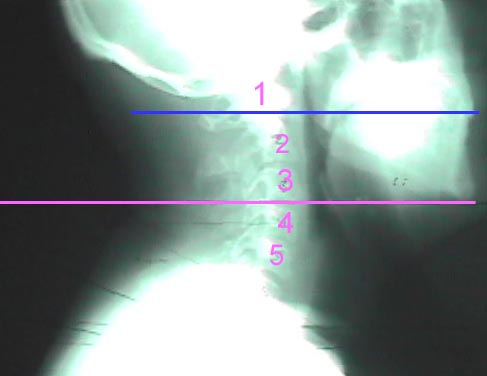

There are several known landmarks on the human body. However, since Kennedy was fully clothed, there are only a few correlations that can be made to approximate the level of the collar. One would be the mouth, the other would be the chin. A commonly taken x-ray is called an APOM (Anterior-Posterior Open Mouth). This view allows the examiner or radiologist to view the C1-C2 joint spaces in the upper neck. When taking this x-ray, the patient is in a neutral position with their back to the film and their mouth open. This removes the lower jaw and teeth from that area, creating a window to visualize C1-2. So, the mouth, in a neutral position, is correlated to C1-2. Another landmark with acceptable variance is the chin. In a random study, I took existing lateral cervical x-rays of 26 adult males and drew level, horizontal lines from the lower margin of the chin backwards through the spine. The patients' ages ranged from 19-59 years of age, with the mean age being 36.3 years old. The vertebral level of the horizontal line ranged from C3-C5. None of the horizontal lines crossed through C6. The mean level of the horizontal line was C4. President Kennedy was of normal facial and neck proportions and it is reasonable to assume that his chin was at the level of C4 in a neutral position.

This is a sample x-ray that was used as part of the study. As you can see, the horizontal line crosses between the 3rd and 4th cervical vertebra. Hence, this patient received a value of 3.5. The blue line represents a line through the mouth. Though difficult to see, this line crosses both C1 and C2. The first two cervical vertebrae are considered non-typical vertebra. They are commonly referred to as the Atlas (C1) and the Axis (C2) due to their shape and function. The joint between C1 and C2 allows us to turn our heads to a large degree.

This collage demonstrates the results of the anatomical study. The pink line represents the 'chin line' and is representative of C4 in the cervical spine. The blue line, or 'mouth line' indicates the level of C2, or the C1-C2 articulation to be most accurate. But, for all practical purposes and ease, we will refer to it as C2. The last picture is a still capture from a film taken during the motorcade in Dallas on November 22, 1963. The blue line crosses the earlobe because Kennedy's head is tilted to the right, thereby lowering the ear. This does not affect the vertebral alignment. X-rays are taken with the head tilted to the left or right with the mouth open as in a neutral film. These films demonstrate abnormal movement in the joint due to fracture. The important concept to remember is that the tilt of the head is insignificant.